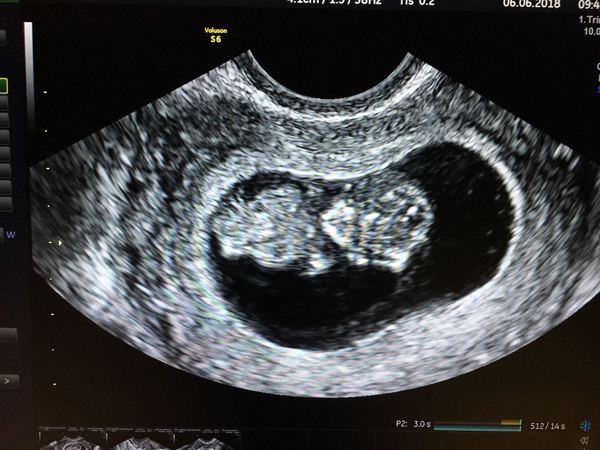

Yay I done it! This is our little one at 9+4 he/she was moving lots so was hard to get a good picture but to me it’s perfect - keep looking all the time.

@merrz it’s kind of up to you, I was so nervous before and almost wimped out but so so so pleased I didn’t.

Gorgeous photo @LJFM2B great you have an active little baby in there! Congrats 😍